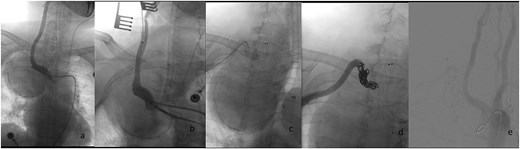

Considering the serious symptoms of chest pain and dyspnea, which indicated that the SAA might rupture at any time and could cause acute airway obstruction, emergency surgery was performed. The procedure was as follows (Fig. 2): Angiography was conducted immediately following a retrograde right femoral artery approach. The angiography showed a gourd-shaped calcification near the mediastinum in the upper lobe of the right lung, and the brachiocephalic trunk artery (BA) and the right common carotid artery (CCA) were well visualized. An SAA erupted from the right beginning of the right subclavian artery, and the aneurysm was gourd-shaped; the inflow artery was at the lower layer, and the outflow artery was at the upper layer. Based on these findings, we decided to place a covered stent through the BA and CCA. However, the diameter of the BA was 13 mm and the CCA was 8 mm. The normal covered stents were of equal diameter. Therefore, we decided to use a descending diameter covered stent, Endurant II LIMBS, which is commonly used in the endovascular treatment of abdominal aortic aneurysms. As the delivery length of the stent is only 57 cm, we could not place the stent through the femoral artery. The CCA was the suitable operative approach. The right CCA was dissected out, a retrograde puncture of the right CCA was performed, and a 14F introducer sheath was placed. A 16 mm–10 mm–93 mm Endurant II LIMBS (Medtronic Ireland, Parkmore Business Park West, Galway, Ireland) was implanted through the CCA approach. Immediately after the deployment of the stent grafts, angiography was performed, and no endoleak was observed. The right common carotid artery was sutured with a 6–0 Prolene suture. To assess the condition of the upper aneurysm, angiography was performed through the right brachial artery. The partial cavity of the aneurysm could be visualized, but the origins of the vertebral artery and internal thoracic artery were close to the aneurysm. Therefore, coil embolization of the outflow artery was performed. Considering that this side of the vertebral artery was not dominant, the origin of the right vertebral artery was not protected. Angiography was performed after embolization; no endoleak was found, the BA and the right CCA were well visualized, and the distal subclavian artery was visualized later through the collateral circulation.

Endovascular procedural steps. (a) Pre-interventional angiography identifies the SAA originating from the ostium of the right subclavian artery. (b) Fluoroscopic guidance demonstrates retrograde deployment of the tapered stent-graft through the common carotid artery approach, with real-time angiography confirming appropriate stent positioning. (c) Post-stent angiography reveals residual aneurysm cavity perfusion through persistent outflow tracts. (d) Selective embolization of the outflow artery using detachable coils (chevrons) achieves complete cavity obliteration. (e) Final control angiography documents technical success: Preserved patency of the brachiocephalic trunk and right common carotid artery, absence of endoleak, and delayed opacification of the distal subclavian artery via collateral circulation.